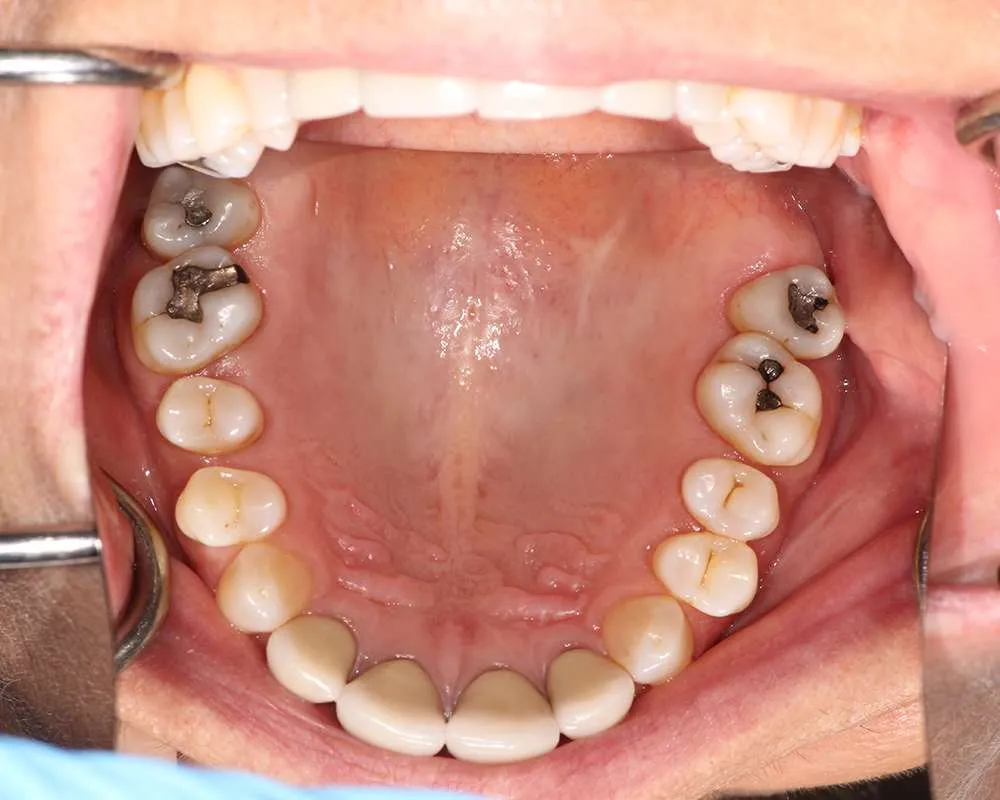

Real Stories, Real Results: Case Studies Showcasing How Our Personalized Approach Transforms Smiles and Lives

Complex Cases

Witness the Remarkable Changes We Can Achieve

The safe removal of mercury fillings is crucial for your health and well-being. At our practice, we follow strict protocols to ensure that mercury amalgam fillings are removed safely and effectively.